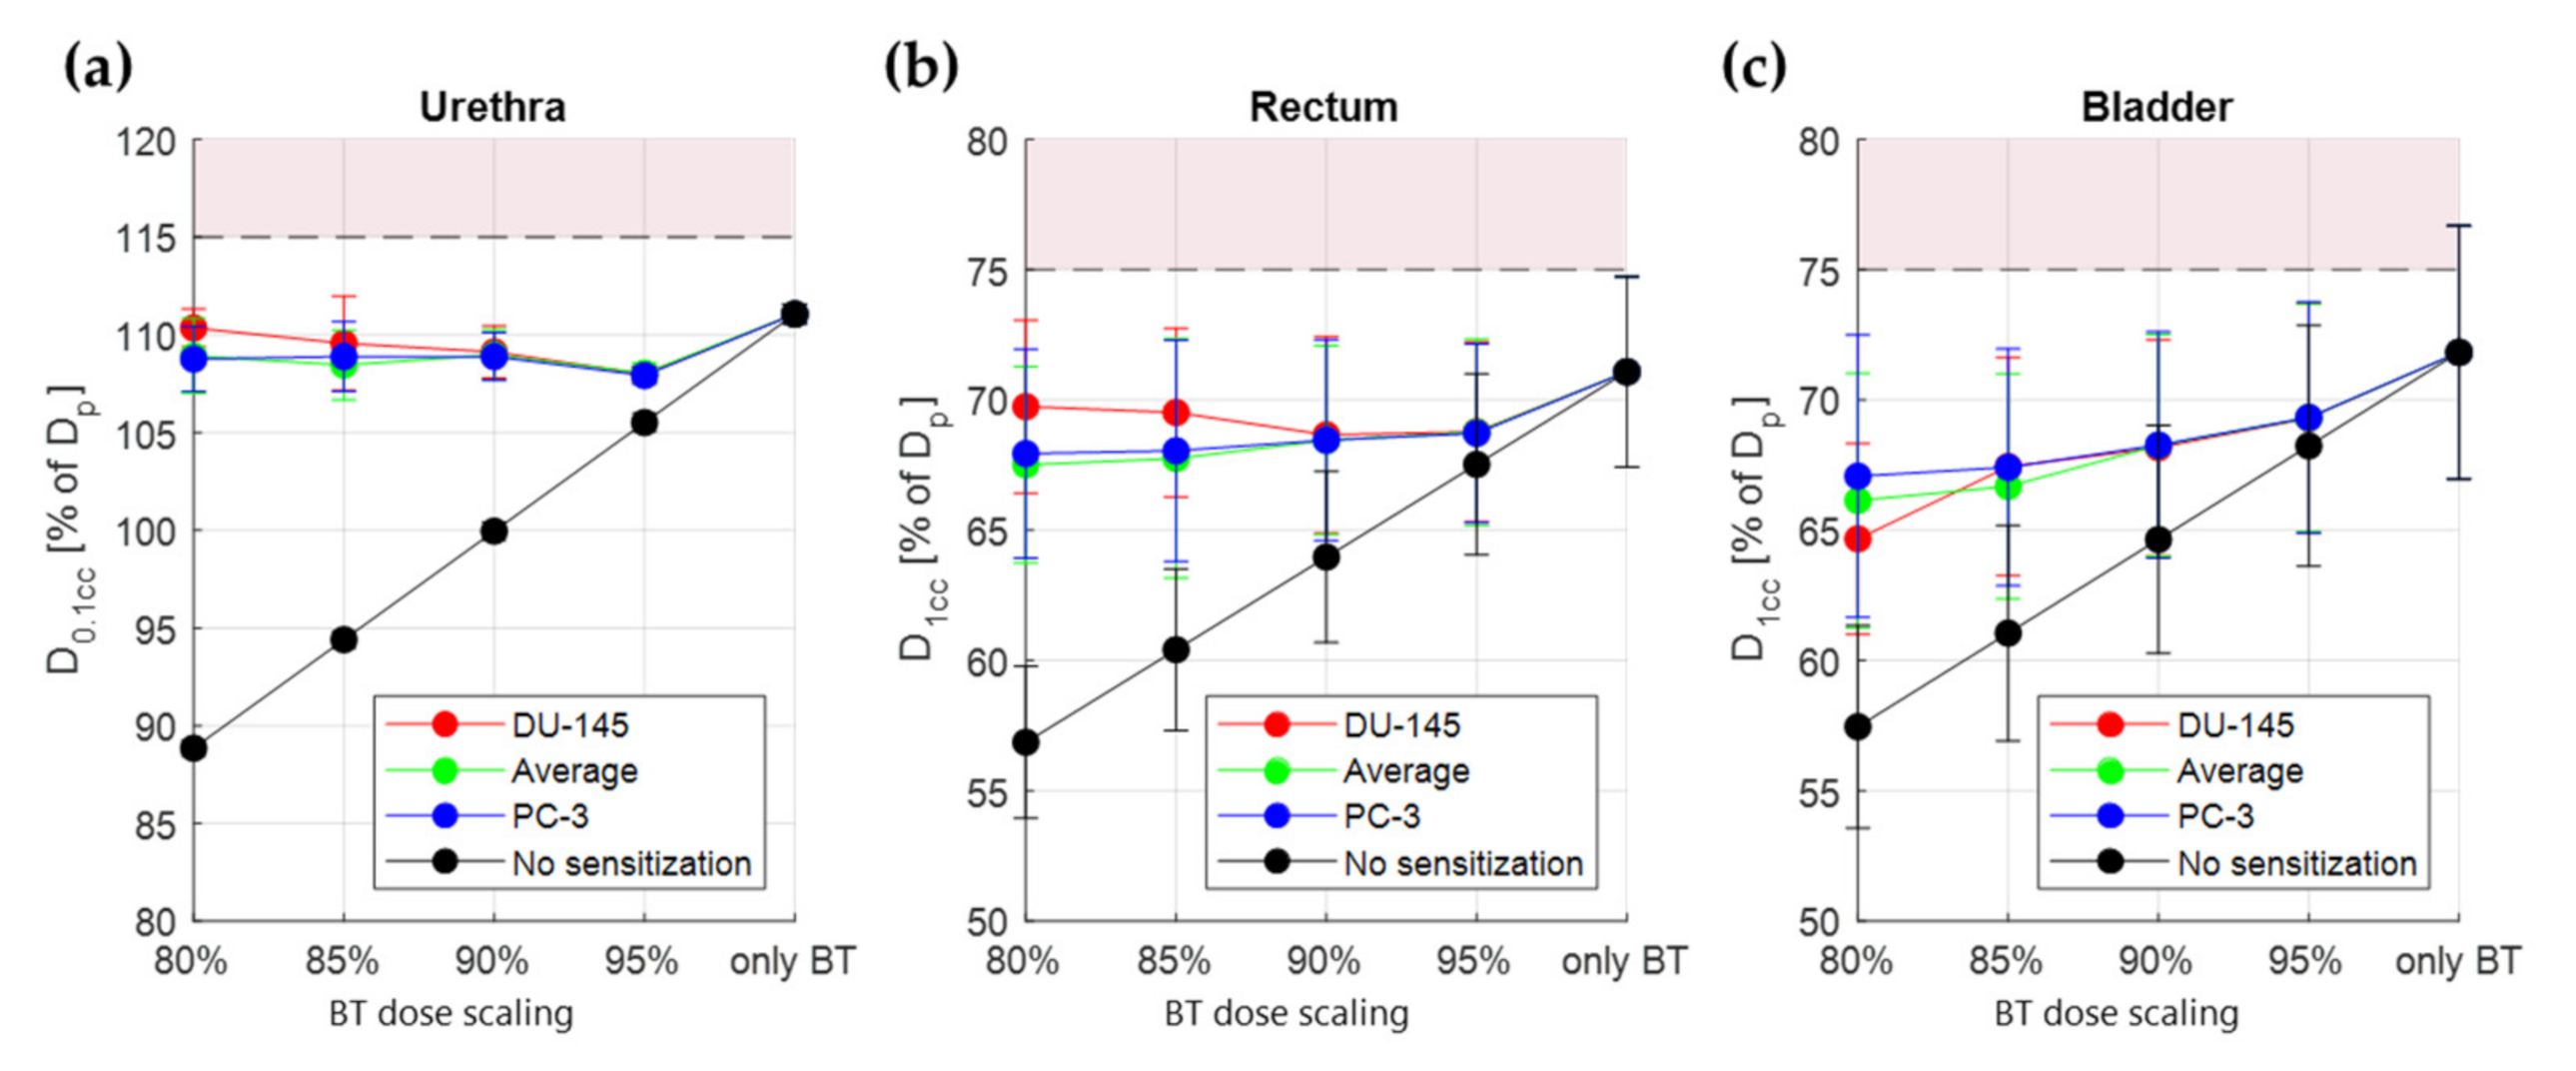

3.3. Treatment Planning Results

| Urethra | D0.1cc | <115% | Hard Constraint |

| Rectum | D1cc | <75% | Hard Constraint |

| Bladder | D1cc | <75% | Soft Constraint |